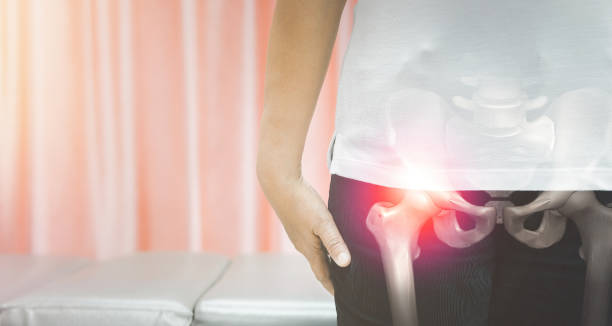

고관절 수술후 회복기간- 수술 후 2주~6주: 물리치료 및 근력 강화

2주~6주 동안은 물리치료와 근력 강화에 집중해야 합니다. 수술로 약화된 근육을 다시 강화하고, 동작 범위와 적응력을 향상시키기 위한 운동을 실시해야 합니다. 이때 꼭 전문가의 도움을 받아야 하며, 개인 차원에 맞는 프로그램을 진행해야 합니다. 무리한 운동을 하지 않도록 조심해야 합니다.